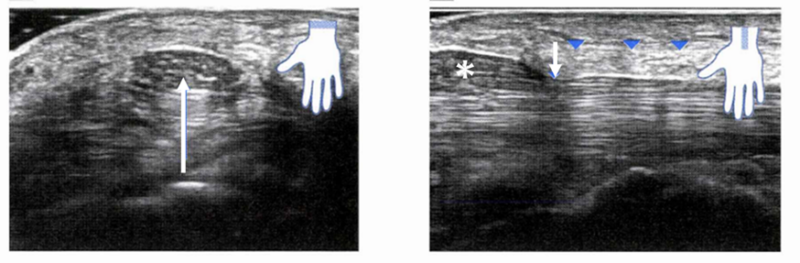

ファーレンテスト(陽性:手関節屈曲位を保つと1分以内に症状が悪化する)などの所見は診断に役立ちますが、必ずしも陽性になるとは限りません。超音波エコー(以下エコーと略す)では、手根管に短軸(手首のしわに平行)でプローブ(肌に直接接触させ、内部構造をみるためのエコーの装置の部品)を当てると、正中神経の腫大(偽神経腫と言う)があると、低エコー(黒っぽい色)が腫大しているのが認められることがあります。ドプラ法(血流をみる方法)を用いると正中神経の奥にある屈筋腱周囲に血流信号がみられることがあり,その場合は、屈筋腱滑膜炎を示唆します。

神経の長軸(指先から肘のラインに平行な軸)での描出においては、圧迫部位が明らかになることもあります。

左図は、手首のしわに沿ってエコーをあてた画像になりますが、正中神経は腫大し、低エコーを呈しています(白矢印)。右図は指先から肘の方向にエコーをあてた画像になりますが、手根靭帯で神経が圧迫され(白矢印)、腫大(*偽神経腫)を認めます。

但し、必ずしも、エコーで正中神経の圧迫が認められるわけではありません。